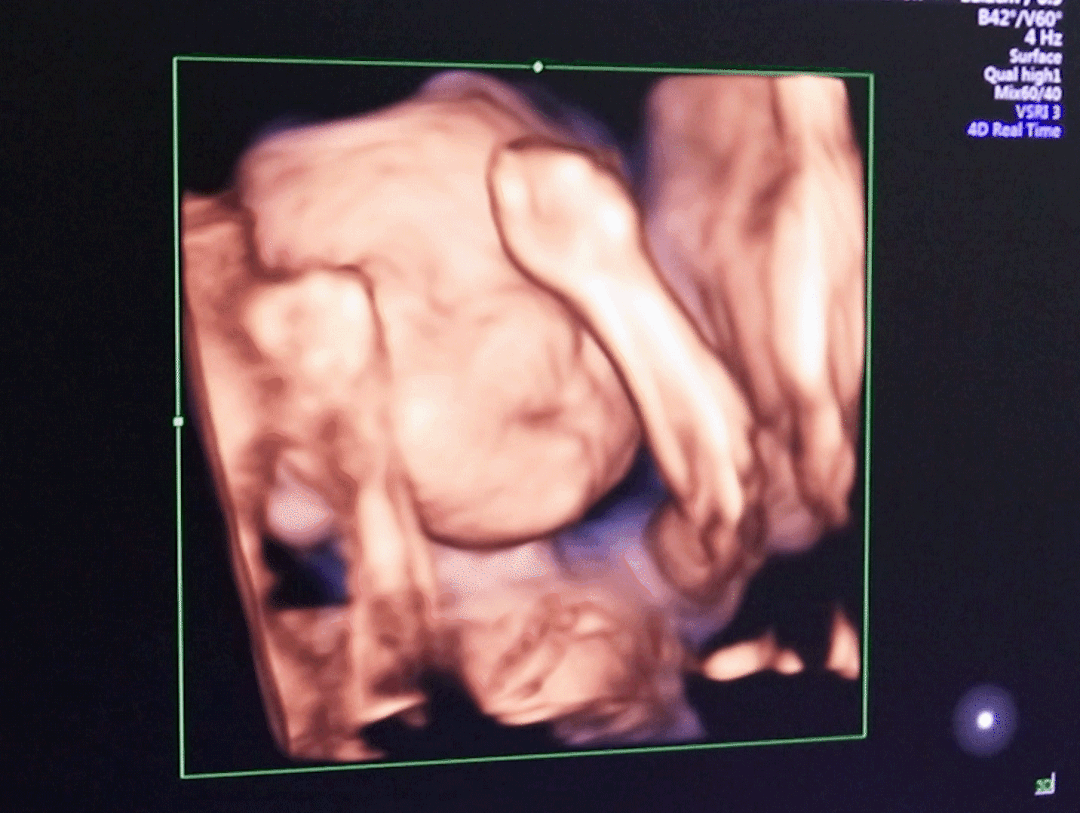

我院引进VOLUSON S6设备,由20年以上临床经验医生操作,可以更加准确、快速地判断胎儿的状况,给予孕妈们专业的意见。

一对一私密诊疗,为孕妈营造温馨舒适的就诊环境;家属陪同观看,记录宝宝成长的过程。

孕妈们做四维彩超检查,一般情况下大概需要30分钟左右,具体的时间是要看妈妈和宝宝的具体情况来看的。

做四维彩超的时间会受到宝宝姿势的影响,如果胎位正检查时间就会相应减少,如果胎位不正、多胞胎医生可能会酌情增加时间。